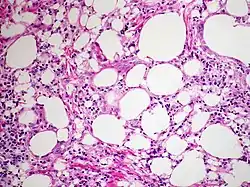

At the microscopic scale foamy macrophages and giant cells are seen in the airways, and the inflammatory response is visible in the parenchyma.